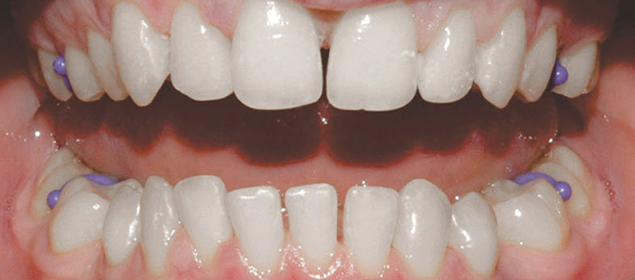

>   Stripping zębów siecznych górnych (wachlarzowaty kształt).

•  Aby poprawić kształt zębów przednich – w przypadku zębów trójkątnych, beczułkowatych czy wachlarzowatych. Dzięki strippingowi można uniknąć powstawania ciemnych przestrzeni między zębami, co poprawia estetykę uśmiechu.